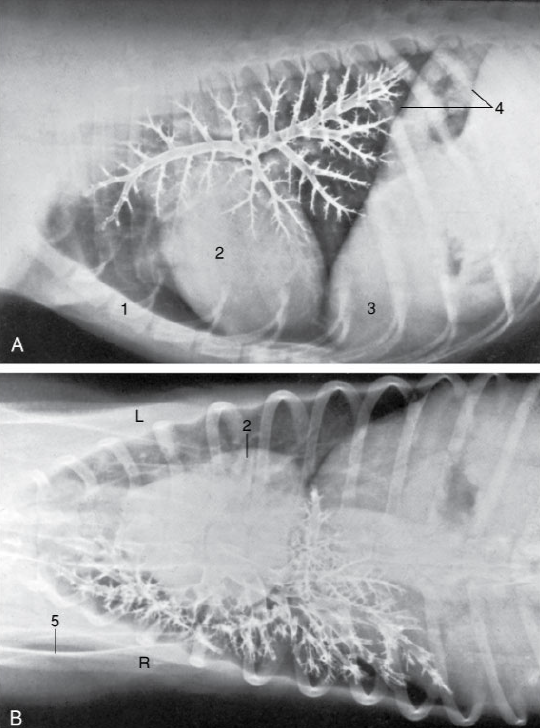

what are the structures shown in the bronchgram

what is the pathway of air from the trachea to lungs

trachea –> left and right primary bronchus (+ tracheal bronchus)